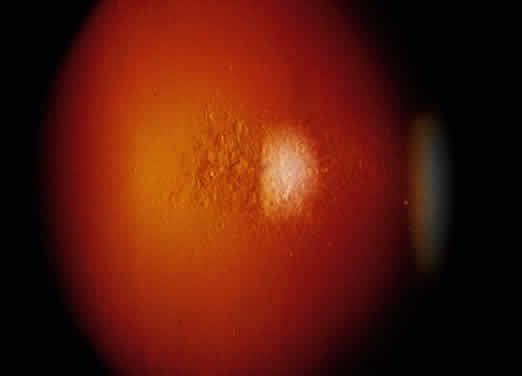

The intraocular inflammation may be acute, but more characteristically it is chronic and usually has few symptoms until vision is affected, or until significant structural changes have occurred. It may affect all parts of the eye. The chronic iridocyclitis is characterized by keratic precipitates that are well defined at the edges and tend to be more concentrated in the peripheral cornea (Fig. 8). The anterior chamber contains cells and flare, and the cells have a great tendency to form cellular nodules, either as keratic precipitates, precipitates on the iris, or at the pupil margin as Koeppe nodules (Fig. 9). The nodules tend to become the site of both peripheral anterior synechiae and posterior synechiae. The cellular reaction is usually sensitive to corticosteroids, but may recur as the corticosteroids are withdrawn.58,65 Treatment responses are further obscured by the frequent tendency for sarcoidosis to undergo spontaneous remission with time, and then recur at a later date. If oral steroids are indicated, moderate to low alternate-day dosages usually control the inflammatory process and produce less systemic side effects.

Fig. 8. Peripheral corneal keratic precipitates with ocular sarcoidosis.

Fig. 9. Sharply defined Koeppe nodule in the pupil of a patient with ocular sarcoidosis.